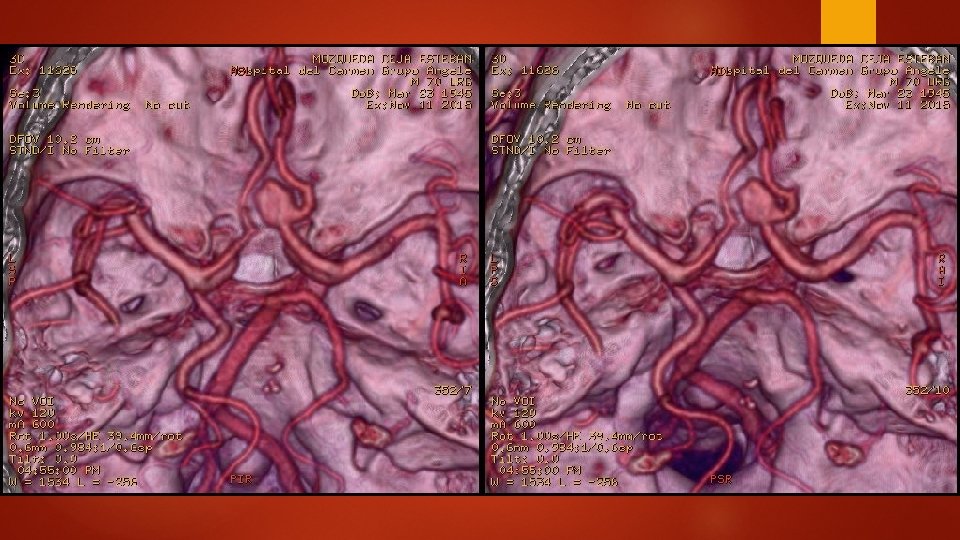

Al llegar al hospital Se decide tomar CT de Cráneo y Angio. CT

Interpretación radiológica Se observa presencia de saculación aneurismática de 6. 2 mm de espesor en la arteria comunicanterior izquierda, en el área de la bifurcación con la arteria cerebral media.